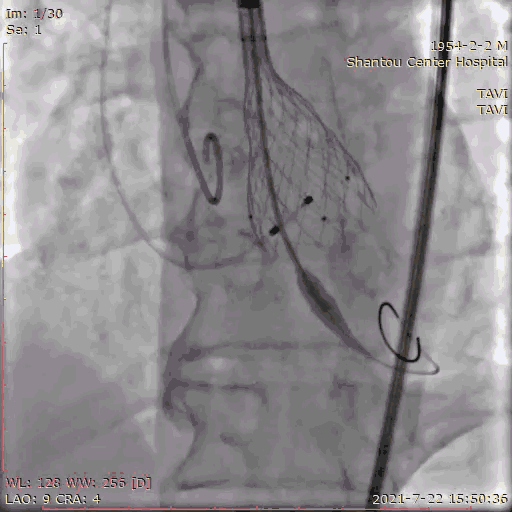

手术流程

主动脉根部造影

跨瓣

180bpm起搏后打球囊,造影,撤球囊,停起搏;23球囊预扩后无漏,冠脉通畅,选择29瓣膜。

球囊预扩张

输送系统定位,标准位置释放

25球囊后扩

无瓣周漏

闭合入路,股浅股深无误